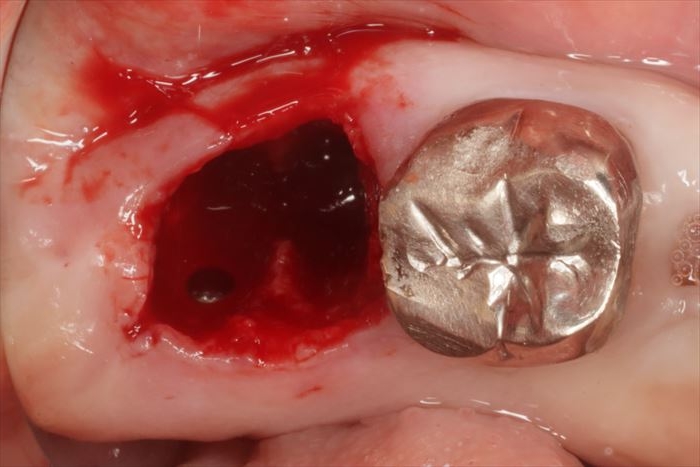

抜歯後治癒不全 抜歯した後の痛みがひかない場合について名古屋市北区の歯医者おくい歯科へ。

抜歯後の不良肉芽組織の除去はとても大切小嶋デンタルクリニック。

親知らずを抜歯した後が黒いのはなぜ?穴は正常に治る?下高井戸駅から徒歩1分の歯医者 下高井戸こたく歯科医院│虫歯・歯周病・一般歯科。

長年放置され悪化した親知らずの抜歯日航ビル歯科室親知らず抜歯なら川崎駅徒歩1分の歯医者。

抜歯後の不良肉芽組織の除去はとても大切小嶋デンタルクリニック。